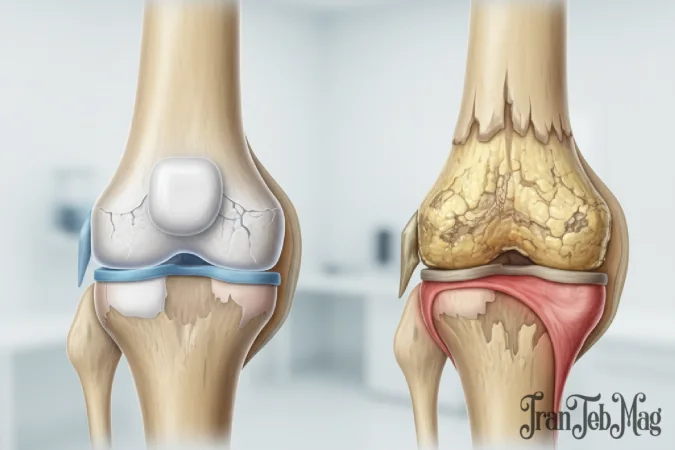

در حالت طبیعی، مفصل زانو با غضروف مفصلی پوشیده شده است؛ این بافت نرم و لغزنده مانند یک لایه محافظ عمل کرده و حرکت استخوانها را بدون اصطکاک و درد ممکن میکند. در آرتروز زانو، این غضروف بهتدریج دچار فرسایش میشود. با کاهش یا از بین رفتن غضروف، استخوانها مستقیماً روی هم ساییده میشوند که نتیجه آن درد، التهاب، خشکی مفصل و کاهش دامنه حرکتی است.

آرتروز زانو یا استئوآرتریت زانو (Knee Osteoarthritis) یک بیماری دژنراتیو (تحلیلبرنده) مفصل است که در آن غضروف مفصلی بهتدریج دچار فرسایش و تخریب میشود. غضروف یک بافت نرم، انعطافپذیر و لغزنده است که انتهای استخوانهای ران و ساق را در محل مفصل میپوشاند و مانند ضربهگیر، مانع ساییده شدن استخوانها به یکدیگر میشود.

در آرتروز، این غضروف به مرور زمان نازک شده یا کاملاً از بین میرود. نتیجه این فرایند، تماس مستقیم استخوانها، ایجاد اصطکاک، بروز التهاب، شکلگیری خارهای استخوانی (استئوفیت) و در نهایت درد و محدودیت حرکتی است.

گرید ۱ – آرتروز خفیف

گرید ۲ – آرتروز متوسط

گرید ۳ – آرتروز پیشرفته

گرید ۴ – آرتروز شدید